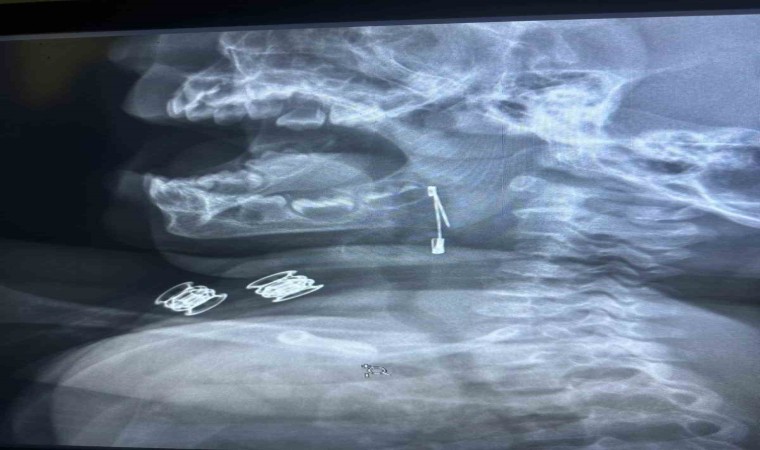

Güroymak ilçesinde 8 aylık bebek, evde bulunan çengelli iğneyle oynarken onu yuttu. Öksürmeye başlayan minik çocuğun, hastanede çekilen röntgen sonucu çengelli iğneyi yuttuğu fark edildi. Güroymak Devlet Hastanesi’nden Tatvan Devlet Hastanesi’ne ambulansla sevki gerçekleşen minik çocuk, Kulak Burun Boğaz Hastalıkları Uzmanı Operatör Dr. Hakan Tuhan tarafından yapılan başarılı operasyonla sağlığına kavuştu. Çengelli iğnenin saplı olduğu soluk borusundan çıkarılan bebek, 2 saatlik gözlemin ardından taburcu edildi.

Konuyla ilgili açıklamada bulunan Kulak Burun Boğaz Hastalıkları Uzmanı Operatör Dr. Hakan Tuhan, “8 aylık bir bebek, Bitlis’in Güroymak ilçesinden tarafımıza danışıldı. Güroymak ilçesinde çekilen röntgen sonucunda çengelli iğnenin soluk borusunun girişinde olduğunu teyit ettik. Yapılan müdahaleler sonucunda çengelli iğneyi çıkardık. Çıkardıktan sonra iki saat kadar gözlem altında tuttuk hastamızı. Daha sonrasında herhangi bir komplikasyonla karşılaşmadık ve sorunsuz bir şekilde taburcu ettik” dedi.